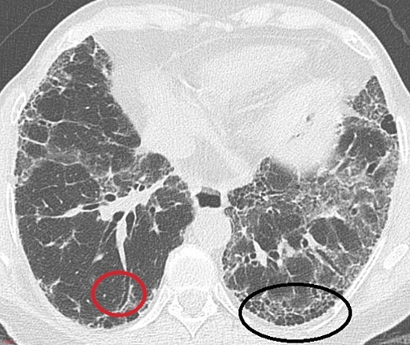

Answer: A) Honeycombing pattern in the lungs

Explanation: IPF is characterised by a honeycombing pattern on CT and lung biopsy. This pattern indicates the presence of fibrotic cystic spaces within the lung, a key diagnostic feature of Usual Interstitial Pneumonia (UIP), which is the histopathological pattern seen in IPF.